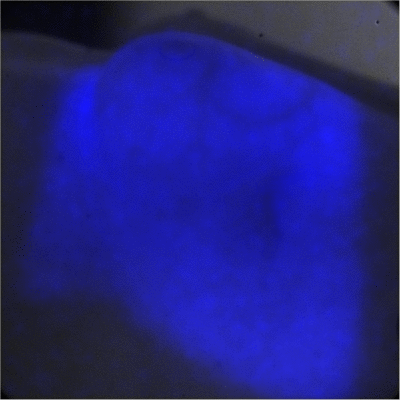

În imagine: o fotografie cu timp lung de expunere a radiaţiei Cerenkov şi a fluorescenţei induse de dizolvarea Fluorescein în apă în timpul iradierii cu ajutorul unui fascicul terapeutic de radiaţii LINAC.

Credit: Adam Glaser

Primul lucru pe care l-au făcut inginerii de la Thayer School of Engineering din Dartmouth a fost să modifice un aparat de fotografiat obişnuit destinat fotografierii pe timp de noapte pentru a-l utiliza pe acesta în scopul obţinerii de fotografii ale unor radiaţii care se deplasau prin apă. Ceea ce a apărut în fotografii este chiar efectul Cerenkov, o lumină strălucitoare de culoare albastră.

Un tratament pe baza unui fascicul de radiaţii este arătat în imaginea de mai sus, acesta fiind aplicat pentru prima dată în cazul oamenilor. Culoarea albastră evidenţiază zona de tratament. Pe măsură ce dozajul radiaţiilor se reduce zona de tratament devine o umbră gri întunecată. Culoarea albastră persistă în zona din dreapta jos a imaginii ceea ce indică un „punct fierbinte" în zona de tratament, locul unde se pot aplica diferite reglaje ale fasciculului de radiaţii pentru a se evita iritarea pielii.